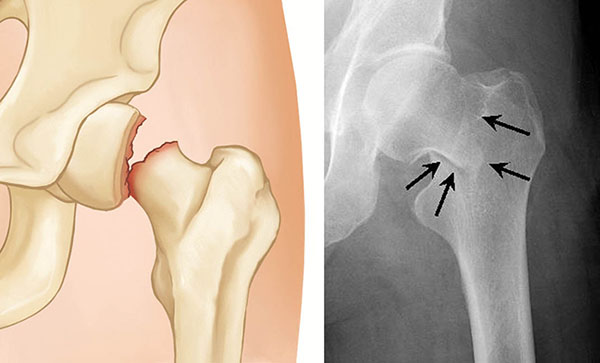

Intertrochanteric fractures occur below the femoral neck in a broader region between the greater and lesser trochanters. The greater trochanter is the bump you feel on the side of your hip. There may be two, three, or even more fracture fragments.

two- and three-part intertrochanteric fractures

Two-part (left) and three-part (right) intertrochanteric fractures